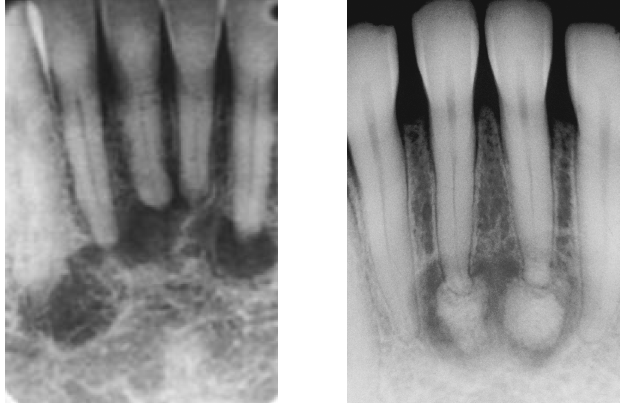

idiopathic osteosclerosis differential diagnosis

contrast with condensing osteitis

if the tooth is non vital - condensing osteosis

condensing osteitis

features of condensing osteitis

non-vital tooth or presence a source of inflammation

widened PDL

sclerosis of bone around roots in response to chronic inflammation

may mimic idiopathic osteoscerosis